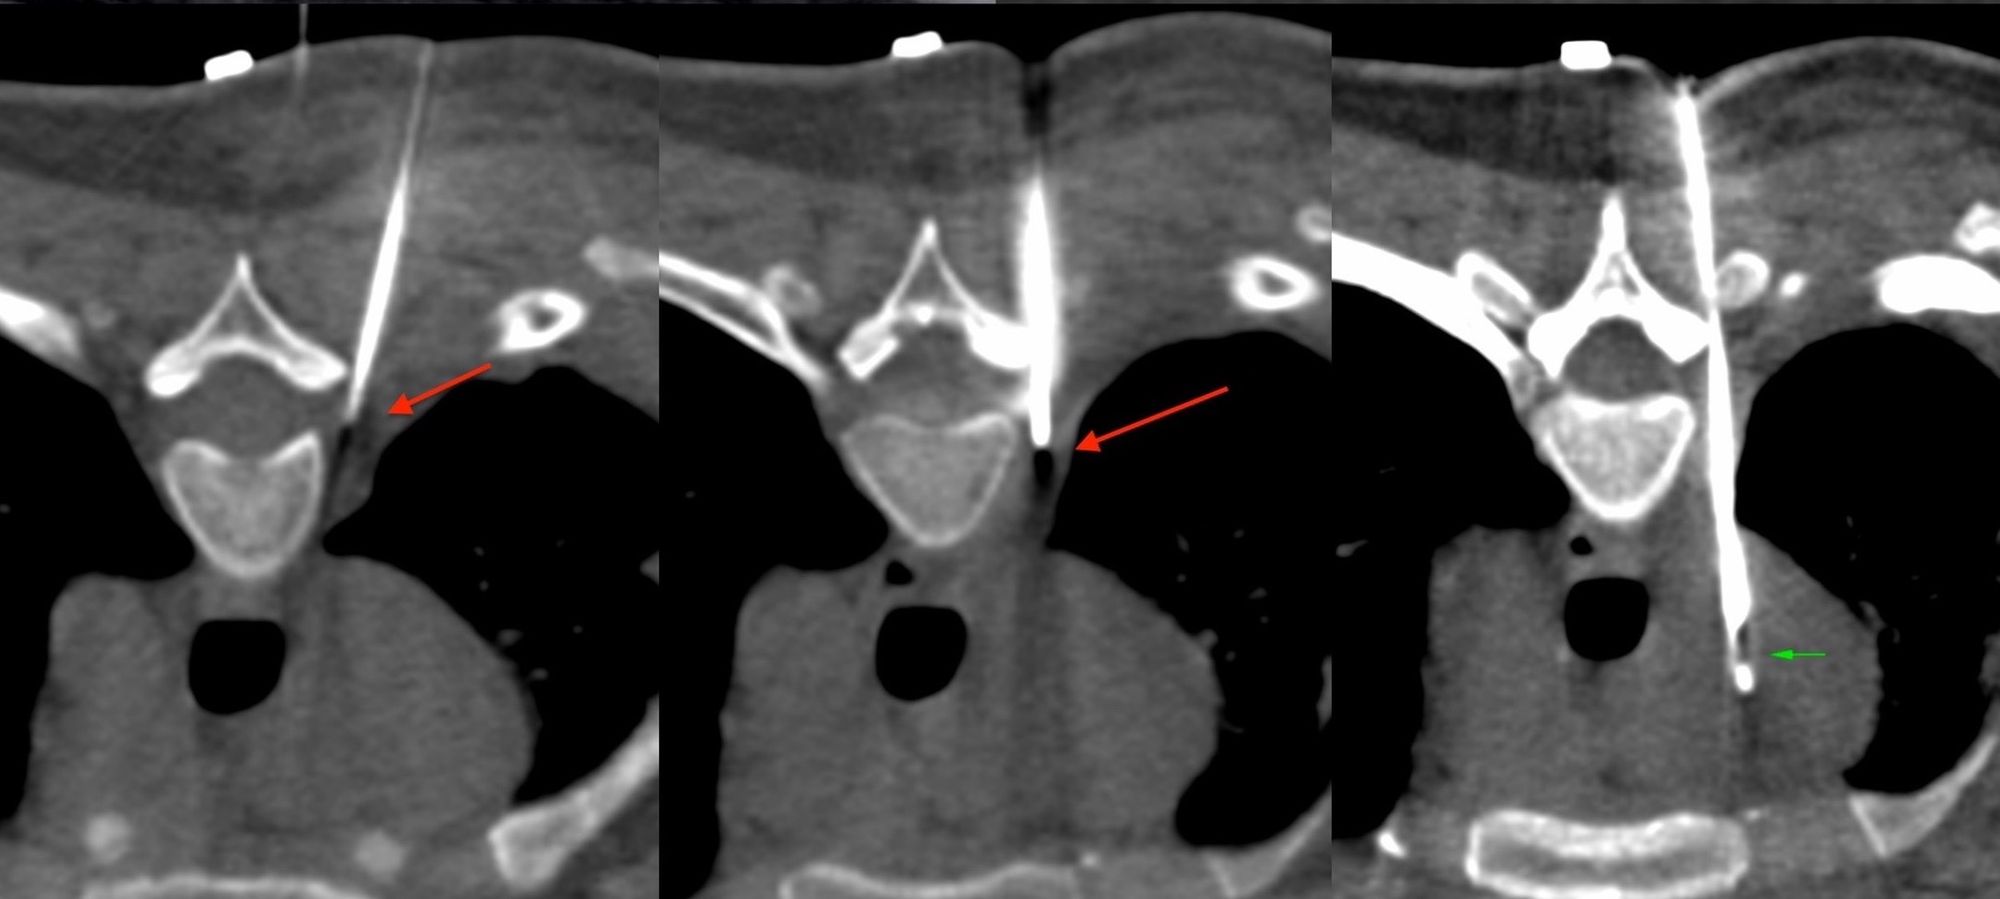

Case 1: Right Paratracheal Node Biopsy - One Stage - Pediatric